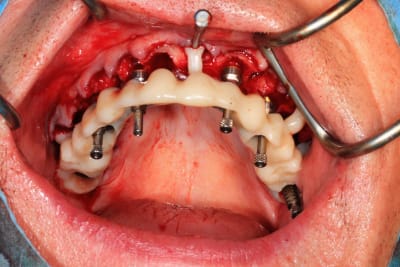

Guide métal avec support clavette, os assez fin : il est prévu un sticky bone complet : donc : lambeau avant extraction, positionnement du guide base et forage des clavettes, positionnement du guide implant, pose des piliers MU, controle des axes prothétique avec le guide pilier, collage des piliers prov sur le bridge a armature métal, occlusion nickel, sticky bone et PRF, sutures suspendues.

Voilà les photos du cas , avec un peu de retard.

06C757A0-0679-4A5E-A2AD-9E867A3CB080.jpeg

65672A94-F454-46C1-A2A7-47927485B543.jpeg

143DCC8C-EA6F-4EE5-9915-F12A33C377B9.jpeg

F8362BF2-81BC-455C-BFD0-A9FE9451F3F4.jpeg

91CE34AF-EDB6-436D-8B12-726F81FC0CB1.jpeg

4060EC60-1F78-4778-B0E3-5FE470671FDF.jpeg

F4ECCBAA-30DE-407C-AAD1-02D226210CC9.jpeg

C4C89A41-3628-4190-A864-AFFC591089BF.jpeg